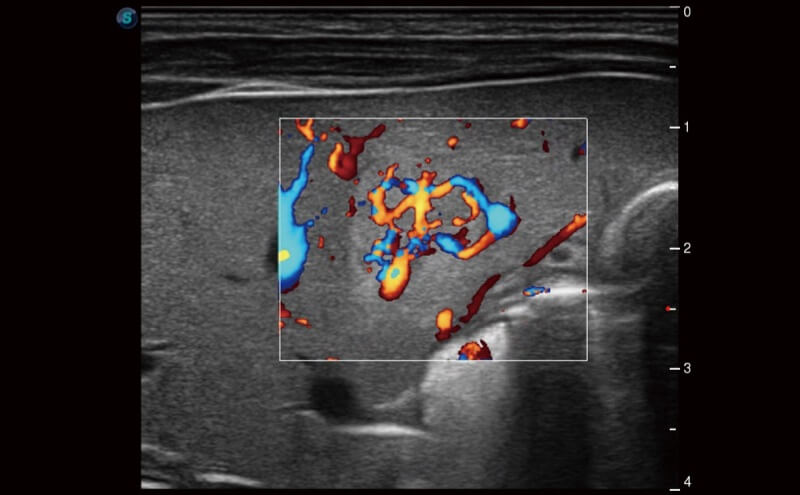

Ultraschall wird immer vielseitiger und übernimmt immer mehr klinische Aufgaben. Als Vorreiter, der Ärzten dabei hilft, mehr zu erreichen, ist ELITE mit einer umfassenden Palette fortschrittlicher Funktionen für die Allgemeine Bildgebung, Gynäkologie/Geburtshilfe, Kardiologie und mehr integriert.

Ultraschall wird immer vielseitiger und übernimmt immer mehr klinische Aufgaben. Als Vorreiter hilft ELITE den Ärzten dabei, mehr zu erreichen, indem es mit einer umfassenden Palette fortschrittlicher Funktionen ausgestattet ist, die die allgemeine Bildgebung, die Geburtshilfe/Gynäkologie, die Kardiologie und vieles mehr abdecken.